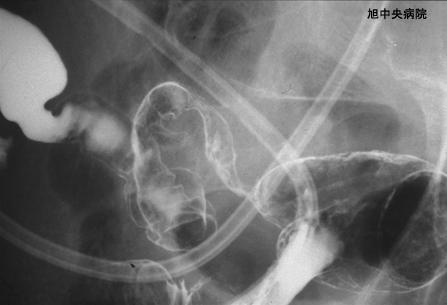

일레우스 증상을 보인 허혈성 소장염의 수술예 (증례제시:치바현 아사히시 아사히중앙병원)

염증성 및 궤양성질환/허혈성 장염(혈전증 포함)

소장/회장

X-P

40이상